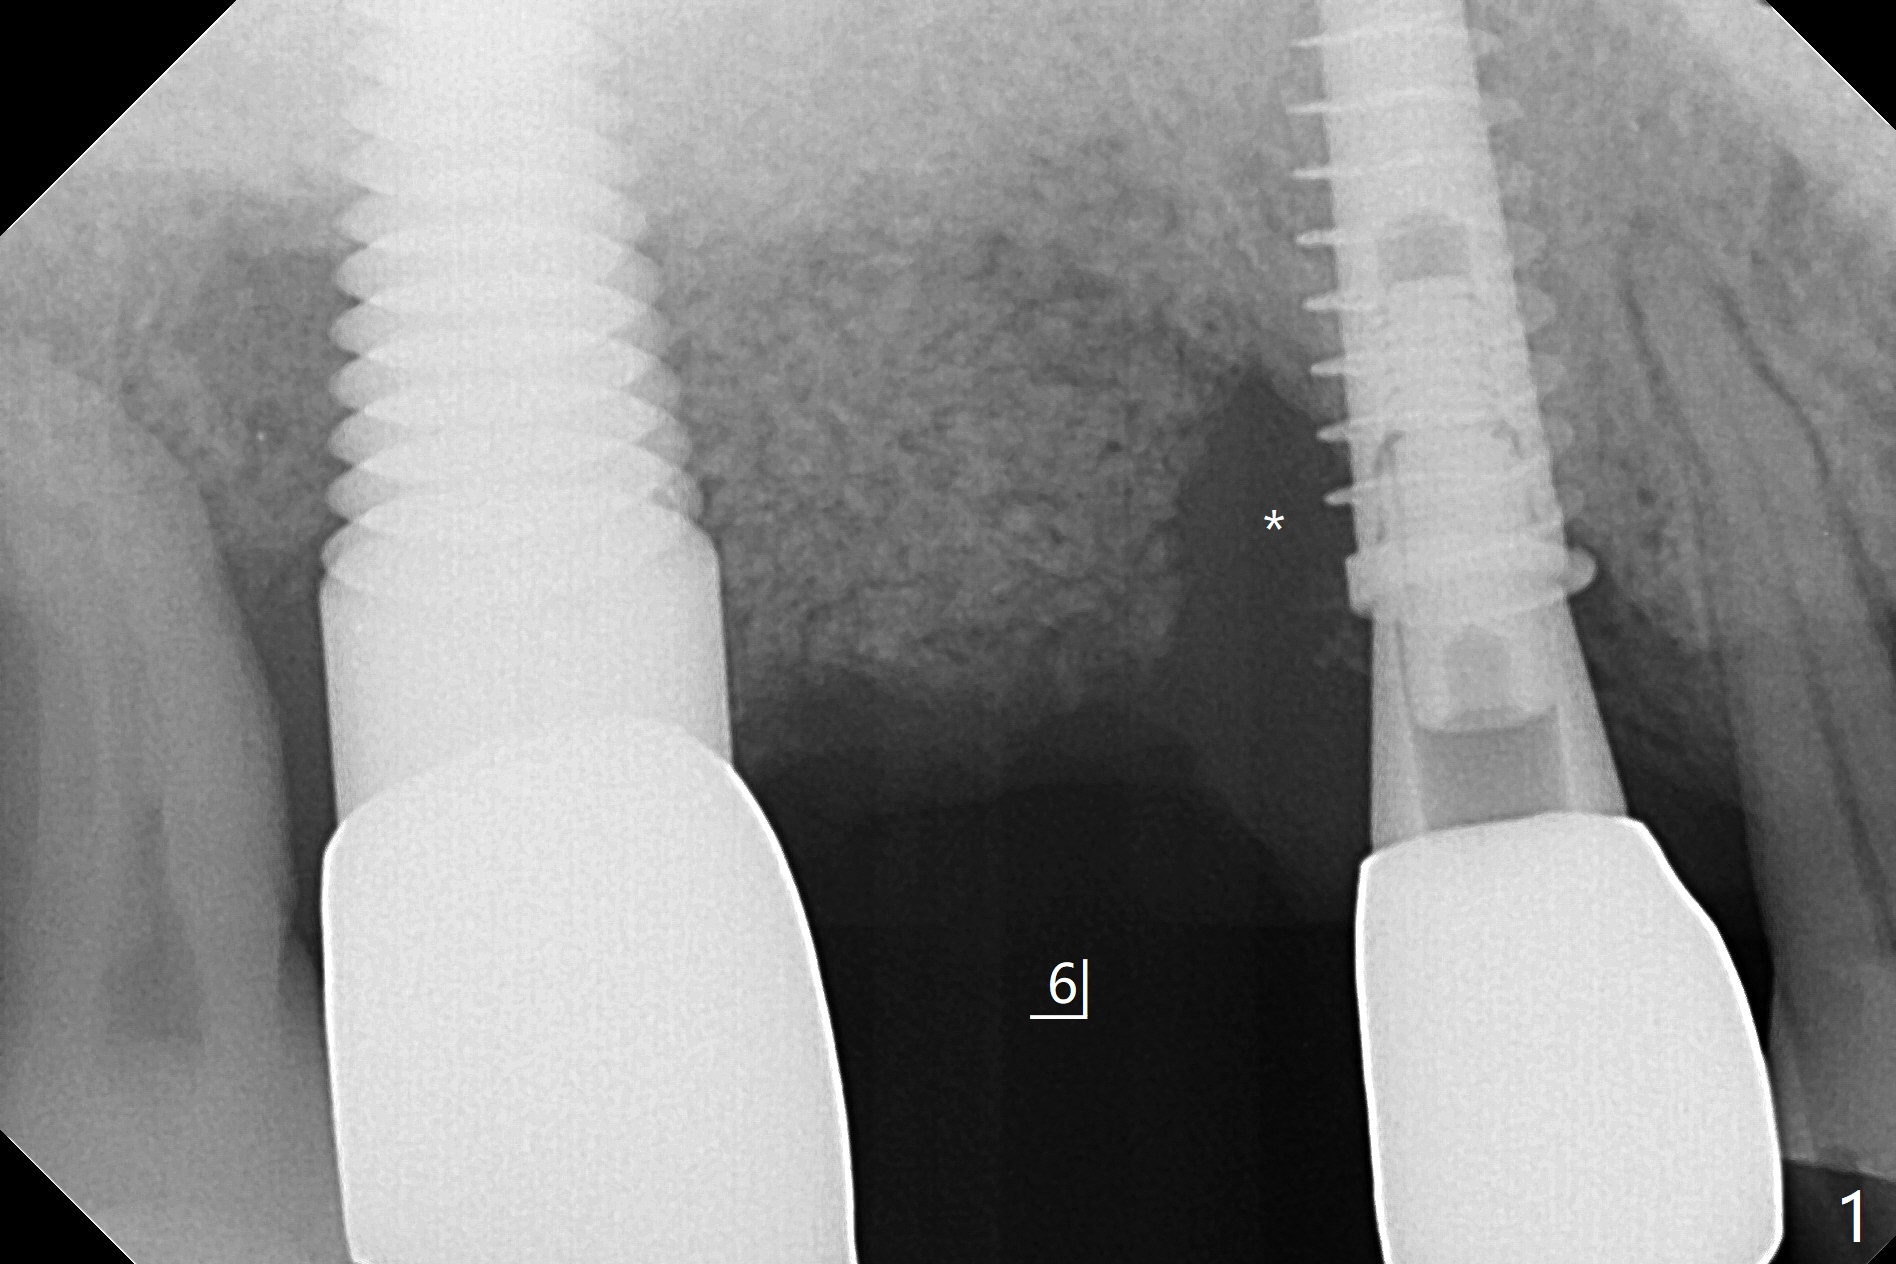

51岁男(牙周炎,咀嚼力大),右上6植体(7x17毫米,即刻种植,当时牙槽窝大,使用大植体,减少骨粉量)使用6年10月后松动,在诊所用手指取出,颊侧牙龈低,刮拔肉芽组织时发现颊侧,腭侧骨壁都缺失,但是没有通入上颌窦,植入粘性骨粉(Vanilla),覆盖一张PRF膜,4-0PGA缝线尽量严密缝合(图一,让口子骨粉有充分血供,相应减少角化龈和骨质高度),然后使用树脂敷料固定(PRF膜很快吸收)。7植体近中螺纹暴露,钛刷清洗后,骨粉放置于表面,而5远中深部螺纹好像暴露,浅部却被牙龈(乳头处)覆盖,所以骨粉无法进入缺失地方(图一:*)。理想的话,应该将牙龈分离(图二:弯箭头),这样骨粉就能进入缺损区域。6愈合后植牙时,用类似方法植骨。术后一周局部卫生好,没有任何不适(图三)。当术后五周树脂敷料取出时,骨粉好像生长不好(图四)。术后两个月伤口愈合(图五),但是骨粉失去不少(图六)。Return to No Caries Xin Wei, DDS, PhD, MS 1st edition 02/09/2021, last revision 08/09/2021